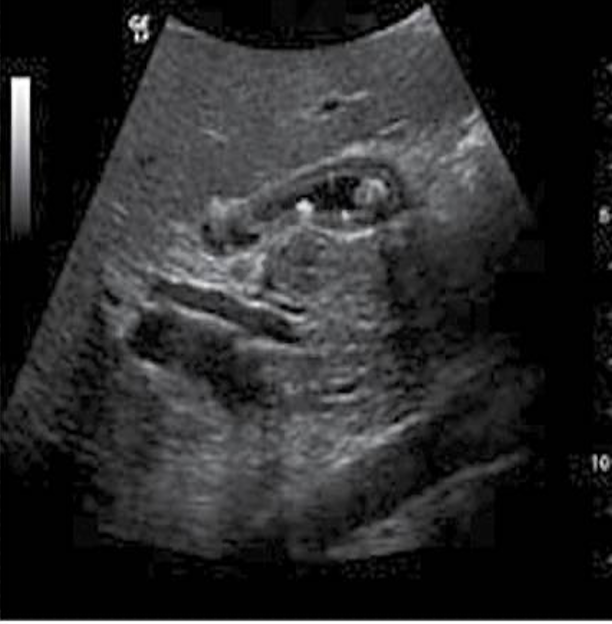

Stones within the common duct are seen if the duct is dilated. The small echogenic focus (arrows) is well seen within the duct in this transverse view.